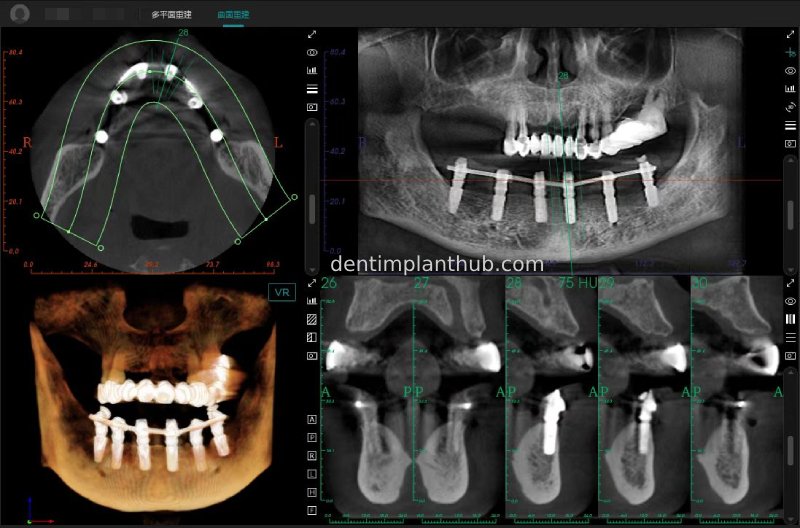

A review of the CBCT on 6/10/23 was more promising and a surgical plan was subsequently drawn up.

46

44

42

32

34

36

General schematic of the surgical programme

Detailed list of implant types and composite abutments to be prepared.

46 tooth position, implant model number 4810, RC series straight composite abutment;

44 tooth position, implant model number 4110, RC series straight composite abutment;

42 tooth position, implant model number 4110, RC series straight composite abutment; alternate implant model number 3310, alternate NC series straight composite abutment;

32 tooth position, implant model number 4110, RC series straight composite abutment; alternate implant model number 3310,. Alternate NC Series Straight Composite Abutment;

34 Dental Position, Implant Model No. 4110, RC Series Straight Composite Abutment;

36 Dental Position, Implant Model No. 4808, RC Series Straight Composite Abutment;